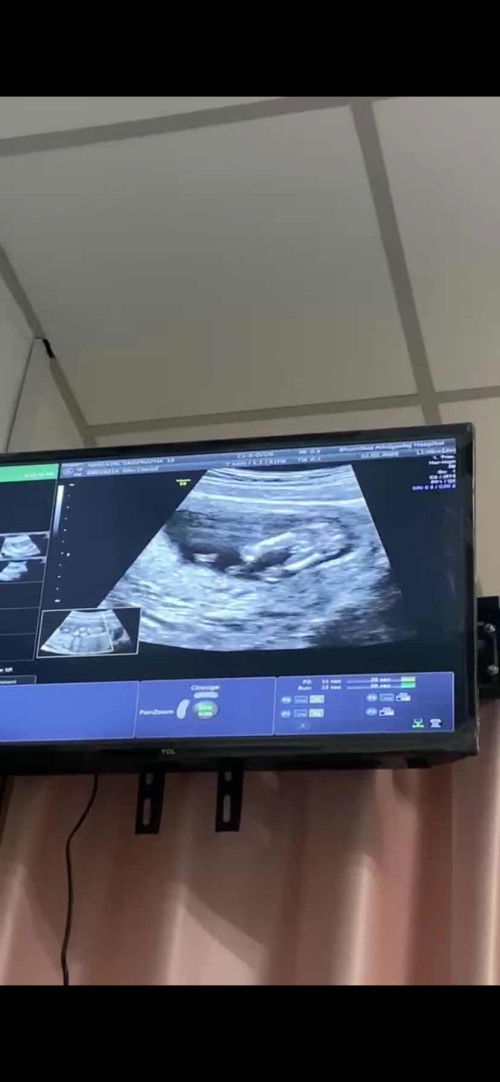

สอบถามแม่ๆค่ะ

ไปรพ. ตอน5สัปดาห์3วัน อัลตร้าผ่านทางช่องคลอด แต่ไม่เจออะไรเลยค่ะ แม้แต่ถุงตั้งครรภ์ก็ไม่เจอ แม่ๆคนไหนมีประสบการณ์มาแชร์ข้อมูลได้นะคะ